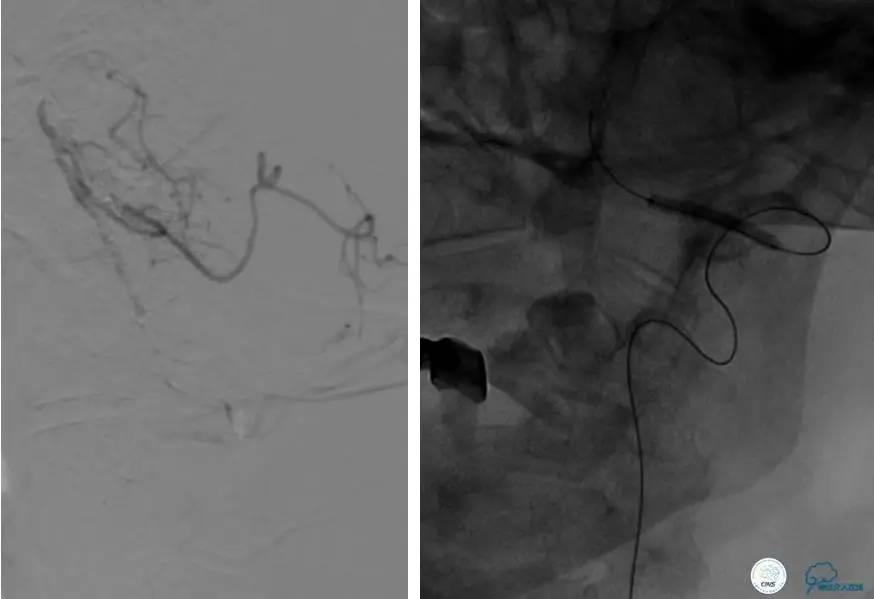

半年后复查造影,无支架内再狭窄,可见弹簧圈,患者恢复至自己柱杖行走。

患者:49岁女性,脑梗死30天。

左侧颈内动脉末端闭塞,末端圆钝且有一定成角,开通难度较大,多次尝试导丝才成功穿过闭塞段。

开通效果很满意,术后症状明显恢复。